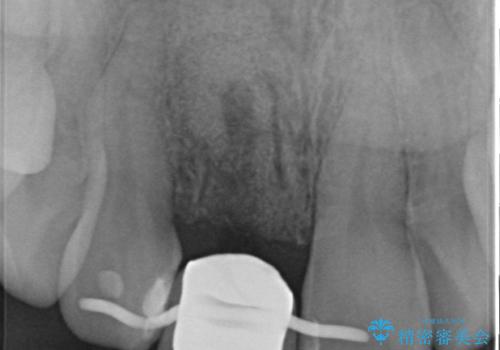

- 目立つ一番前の歯を失い、接着剤で応急処置をしていましたが永続性のある修復を希望され来院されました。

入れ歯・ブリッジ・インプラントによる欠損補綴の方法のうち審美的で取り外しがなく隣の歯を削らない治療を望まれたため、インプラントによる審美・機能回復治療を計画します。

前歯のインプラント治療は適切に行えば、ブリッジのように隣の歯を削らずに審美的で機能的な状態に仕上げることが可能です。

インプラント周囲に十分な骨や歯ぐきの厚みの整備を行うことで、審美的なインプラントの仕上がりを達成することができます。